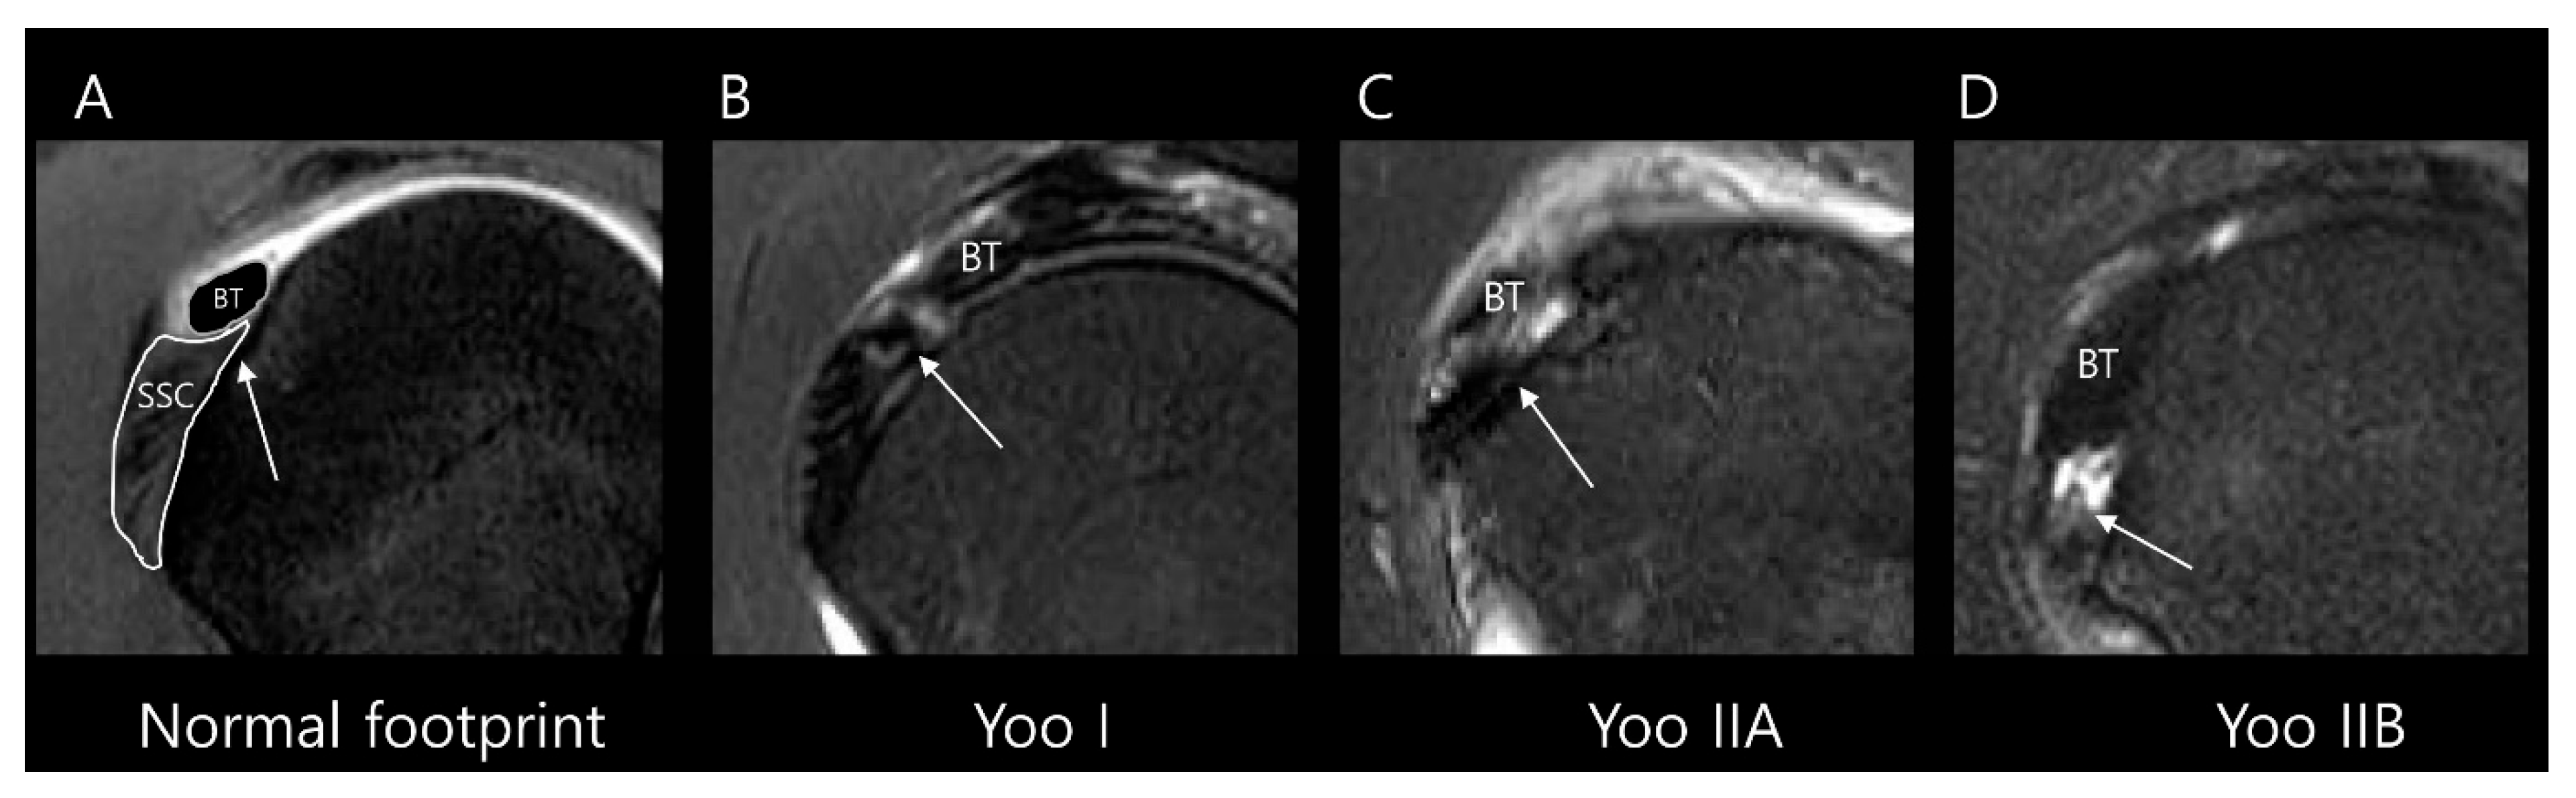

2.3. MRI Analysis

3.2. MRI Findings

| Type I | Fraying or longitudinal split of the leading edge tendon |

| Type II | Partial detachment in the first facet (Lafosse type 1) |

| IIA | ≤50% detachment of SSC in the first facet |

| IIB | >50% detachment of SSC in the first facet without complete disruption of the lateral band |